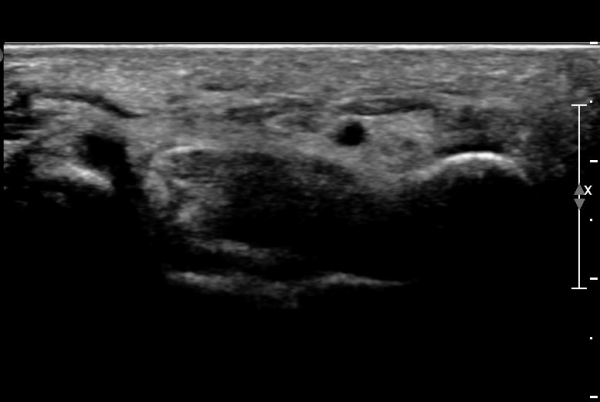

ŽÃËÀÚ¸¦ ¾à°£ ¸»´ÜÀ¸·Î À̵¿ÇÏ´Ï ¿¬ºÎÁ¶Á÷ ºÎÁ¾ÀÌ ´õ¿í ½ÉÇÏ°Ô °üÂûµÇ°í(»çÁø 2),